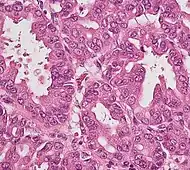

| Pancreatic acinar cell carcinoma (ACC) | 1% to 2% | Granular appearance | ![]() |

|